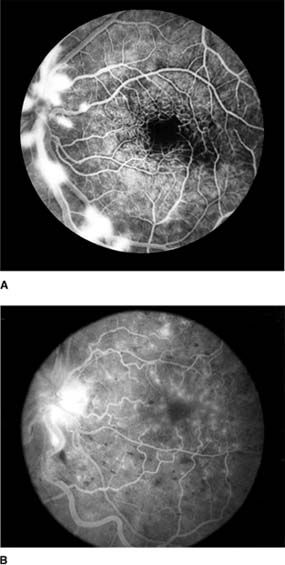

In anterior segment ischemia, patients develop iritis, intraocular pressure changes, and pupillary abnormalities. In retinal ischemia (Figure 15-12A), patients show evidence of capillary dilation and hemorrhages, capillary occlusion, new vessels at the optic disk, and cotton-wool spots.

Figure 15-12: A: Fluorescein angiogram of left fundus in a patient with chronic ocular ischemia secondary to Takayasu's disease. Note capillary dilation, leakage of dye, retinal hemorrhages, cotton-wool spots, and neovascularization of the optic nerve head. B: Fluorescein angiogram, showing leakage at optic disk and macula in a patient with chronic ocular ischemia secondary to dural arteriovenous fistula.

Carotid Cavernous Fistula

Carotid cavernous fistula results from a communication between the carotid artery or its branches and the cavernous sinus, producing characteristic vascular signs. Direct carotid fistulas are usually acute, florid, and posttraumatic, whereas fistulas from dural vessels are usually chronic, mild, and not associated with trauma. Clinical features include elevated intraocular pressure, dilated conjunctival vessels, dilated retinal vessels with hemorrhages and fluorescein leakage (Figure 15-12B), ophthalmoplegia (usually lateral rectus), and bruit. computed tomography (CT) and magnetic resonance imaging (MRI) show thickened ocular muscles and a dilated superior ophthalmic vein. The condition must be differentiated from thyroid eye disease, and interventional radiology is the ultimate diagnostic and therapeutic resource.